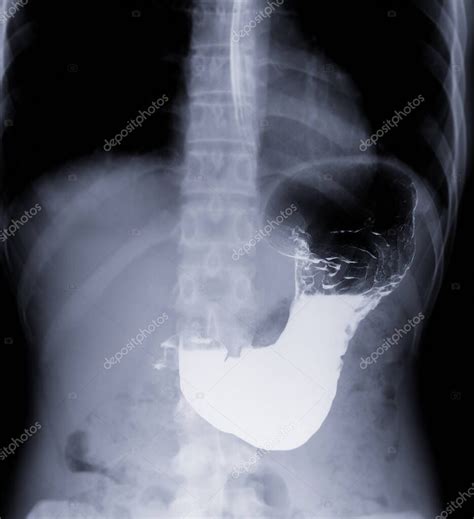

- Tránsito esofagogastroduodenal: Utiliza radiografías con contraste para seguir el paso de los alimentos a través del esófago, estómago y duodeno.